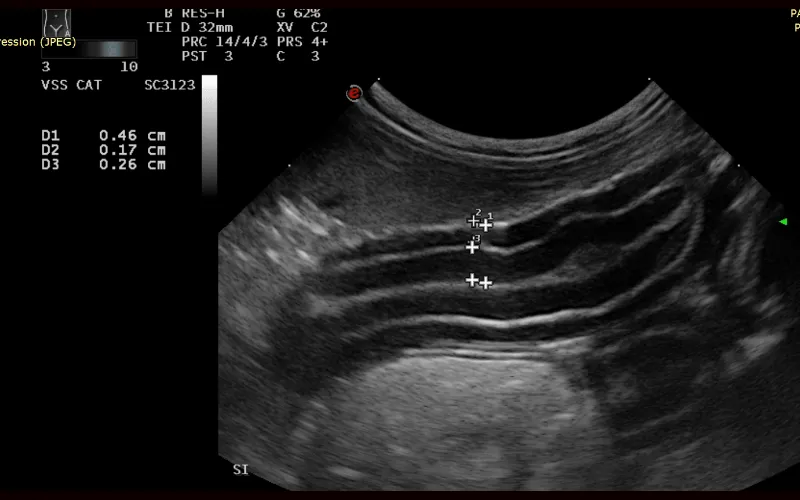

Ultrasound is one of the most valuable technologies we use because it provides a clear, non-invasive view of the organs and structures that need closer assessment. It helps diagnose conditions that aren’t obvious on examination or routine testing.

Different diseases and conditions create distinct patterns that become recognisable on ultrasound, even when physical examination or lab work has been inconclusive. Some findings are diagnostic in themselves, while others provide a strong indication of what is developing and the urgency with which it needs to be addressed.

Ultrasound allows us to examine internal organs without surgery. It helps identify changes in tissue structure and assess how organs interact with each other.

Ultrasound can evaluate abdominal organs, soft tissues and other internal structures. This imaging technique helps us look for abnormalities that may affect a cat’s health.